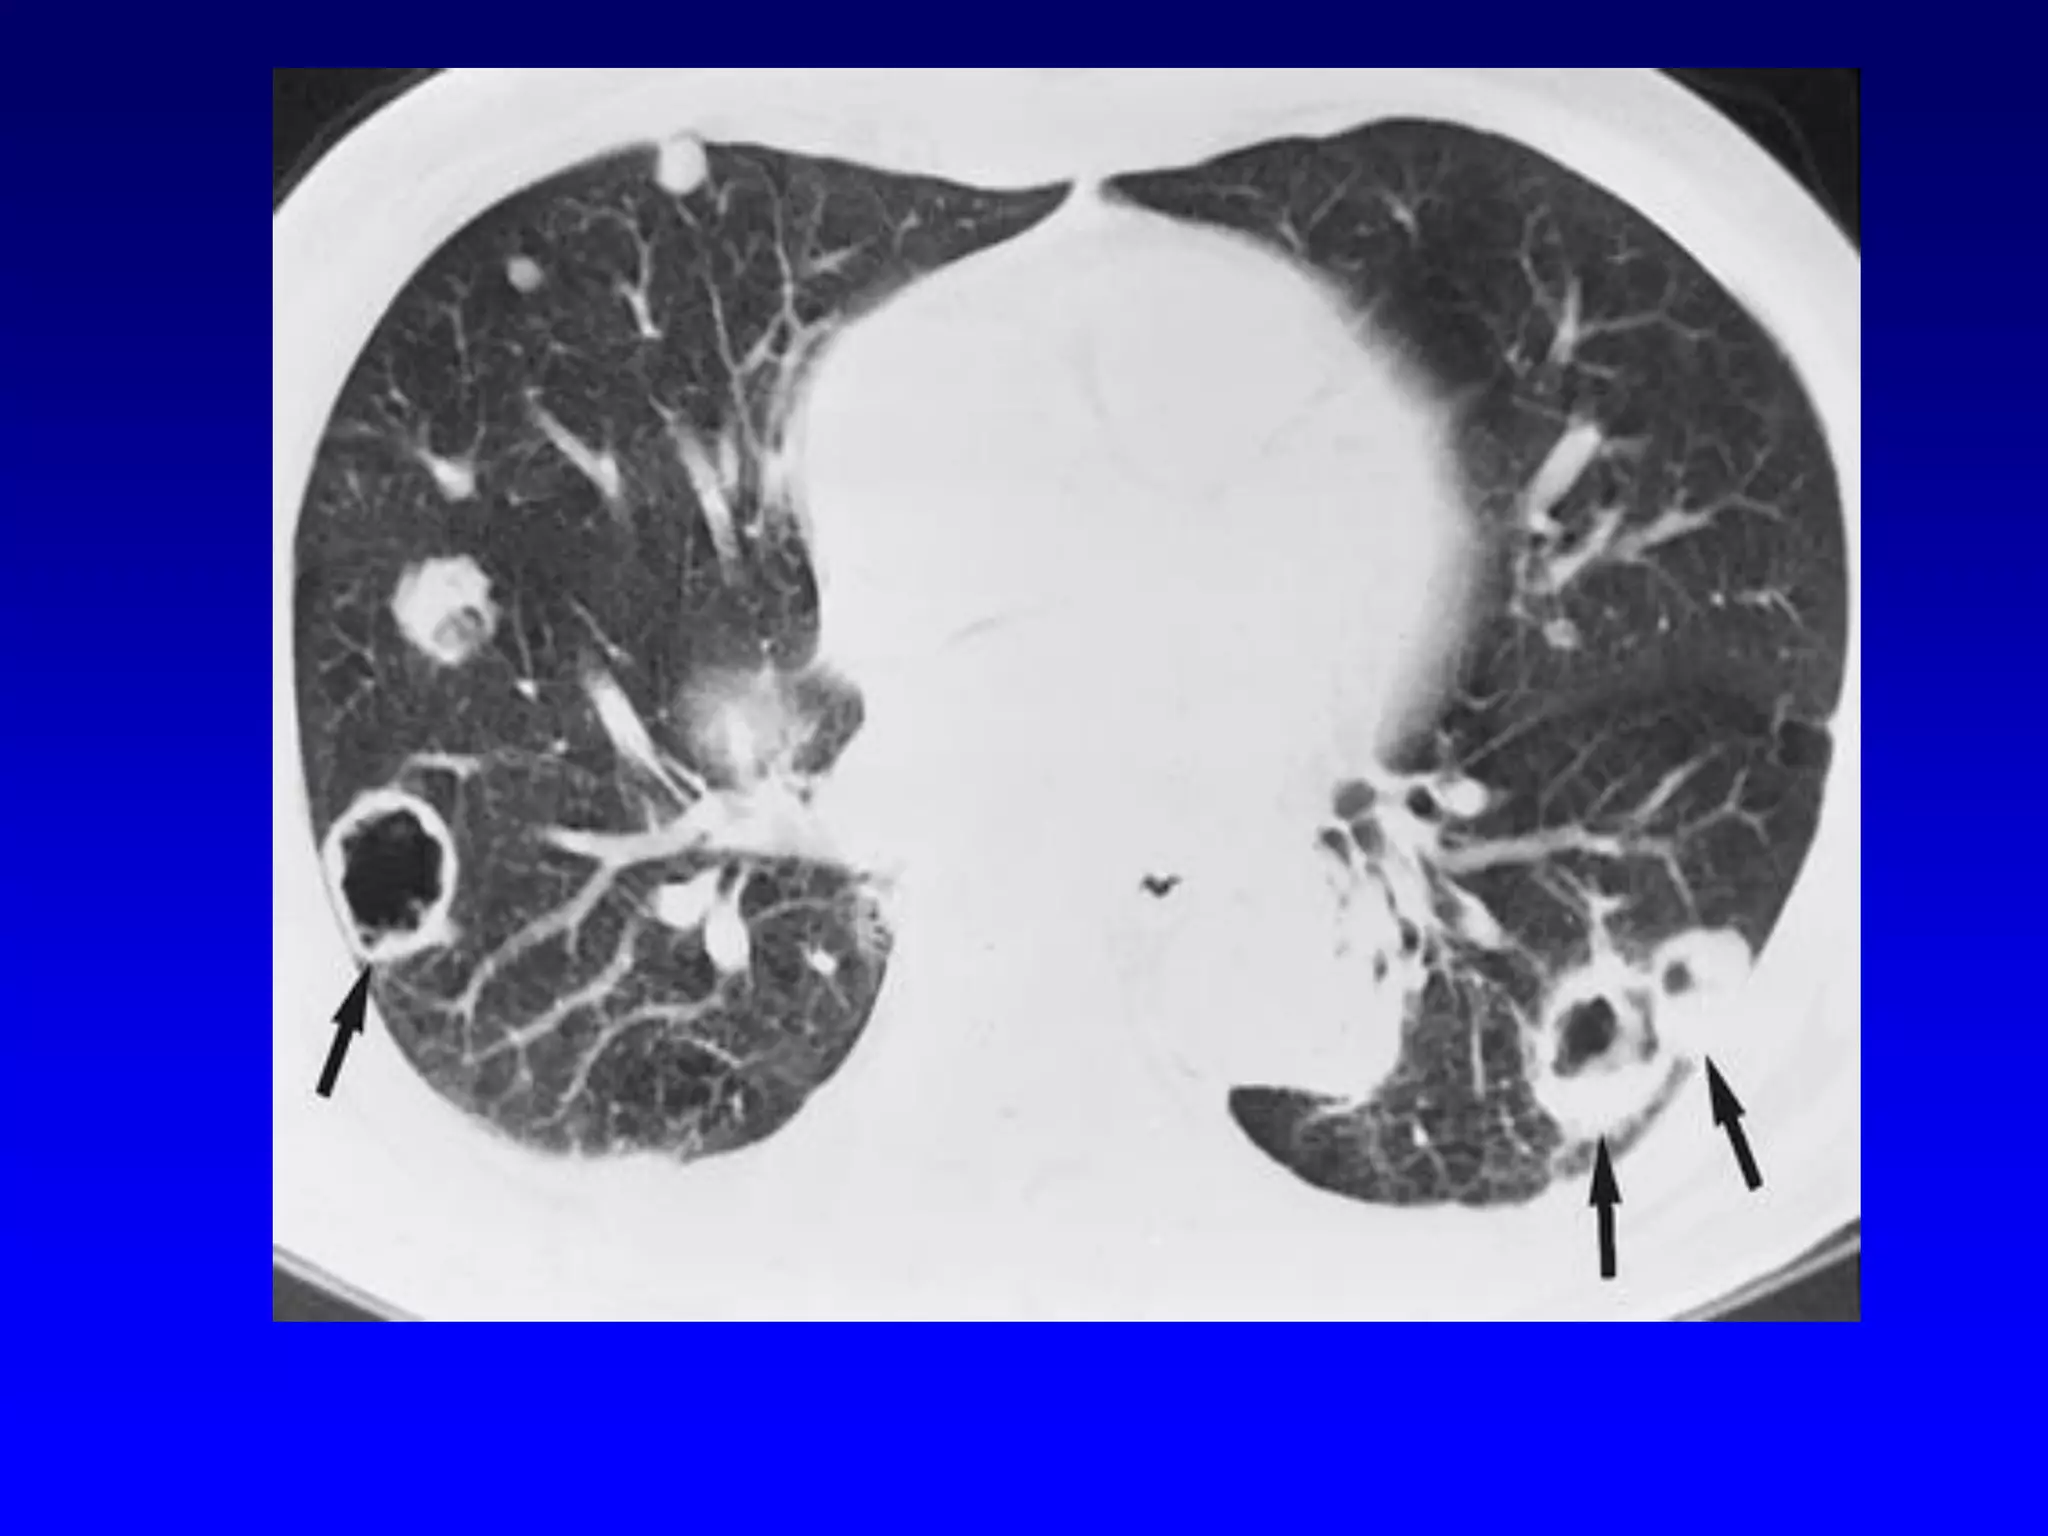

Bronchiectasis

Morphologic criteria on thin-section CT

scans include bronchial dilatation with

respect to the accompanying pulmonary

artery (signet ring sign), lack of tapering

of bronchi, and identification of bronchi

within 1 cm of the pleural surface (27)

(Fig 11). Bronchiectasis may be classified

as cylindric, varicose, or cystic, depending

on the appearance of the affected bronchi.

It is often accompanied by bronchial wall

thickening, mucoid impaction, and smallairways abnormalities